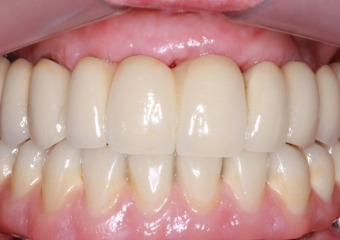

Próteses Fixas Definitivas em Porcelana, em 2013 - Clínica Cliniface

Próteses Fixas Definitivas em Porcelana, em 2013

Imagem Próteses Fixas Definitivas Superior e Inferior, em 2013 - Clínica Cliniface

Imagem Próteses Fixas Definitivas Superior e Inferior, em 2013